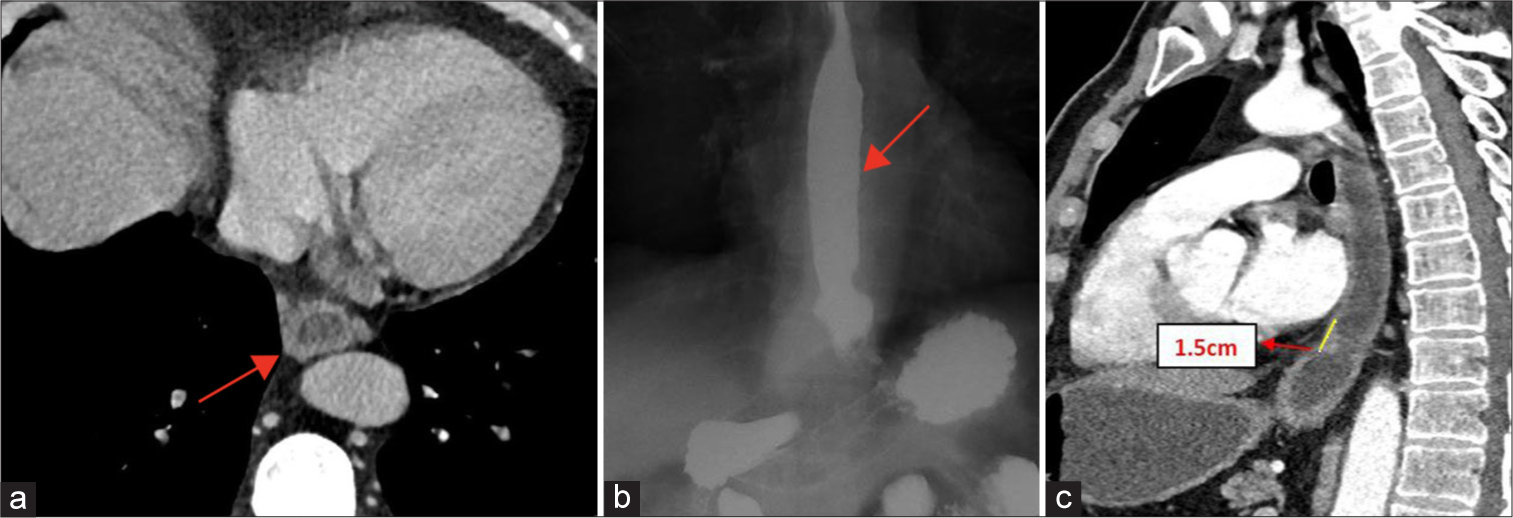

The patient underwent multiple sessions of endoscopic oesophageal dilatations followed by computed tomography and barium swallow.

Figure 5a shows post management computed tomography axial section showing reduced oesophageal wall thickness measuring 5 mm at the site of stricture.

- (a) Post-management computed tomography (CT). Axial section showing reduced esophageal wall thickness (5 mm) (red arrow). (b) Post-management barium swallow Antero-posterior (AP) view showing no stricture, however hiatus hernia was seen as denoted by red arrow. (c) Post-management CT sagittal oblique views showing reduced length of stricture to 1.5 cm with minimal luminal narrowing denoted by yellow line.

Figure 5b shows post management barium swallow antero-posterior view with no residual luminal narrowing.

Figure 5c shows postop management computed tomography sagittal oblique view showing reduced length of stricture in lower thoracic oesophagus measuring 1.5 cm with minimal luminal narrowing denoted by yellow line.